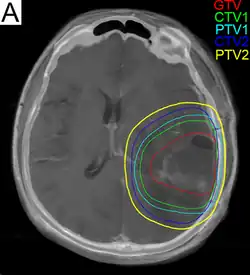

.png)

Subsequent to surgery, radiotherapy becomes the mainstay of treatment for people with glioblastoma. It is typically performed along with giving temozolomide.[10] A pivotal clinical trial carried out in the early 1970s showed that among 303 GBM patients randomized to radiation or best medical therapy, those who received radiation had a median survival more than double those who did not.[77] Subsequent clinical research has attempted to build on the backbone of surgery followed by radiation. Whole-brain radiotherapy does not improve when compared to the more precise and targeted three-dimensional conformal radiotherapy.[78] A total radiation dose of 60–65 Gy has been found to be optimal for treatment.[79]

GBM tumors are well known to contain zones of tissue exhibiting hypoxia, which are highly resistant to radiotherapy. Various approaches to chemotherapy radiosensitizers have been pursued, with limited success as of 2016. As of 2010, newer research approaches included preclinical and clinical investigations into the use of an oxygen diffusion-enhancing compound such as trans sodium crocetinate as radiosensitizers,[80] and as of 2015 a clinical trial was underway.[81] Boron neutron capture therapy has been tested as an alternative treatment for glioblastoma, but is not in common use.